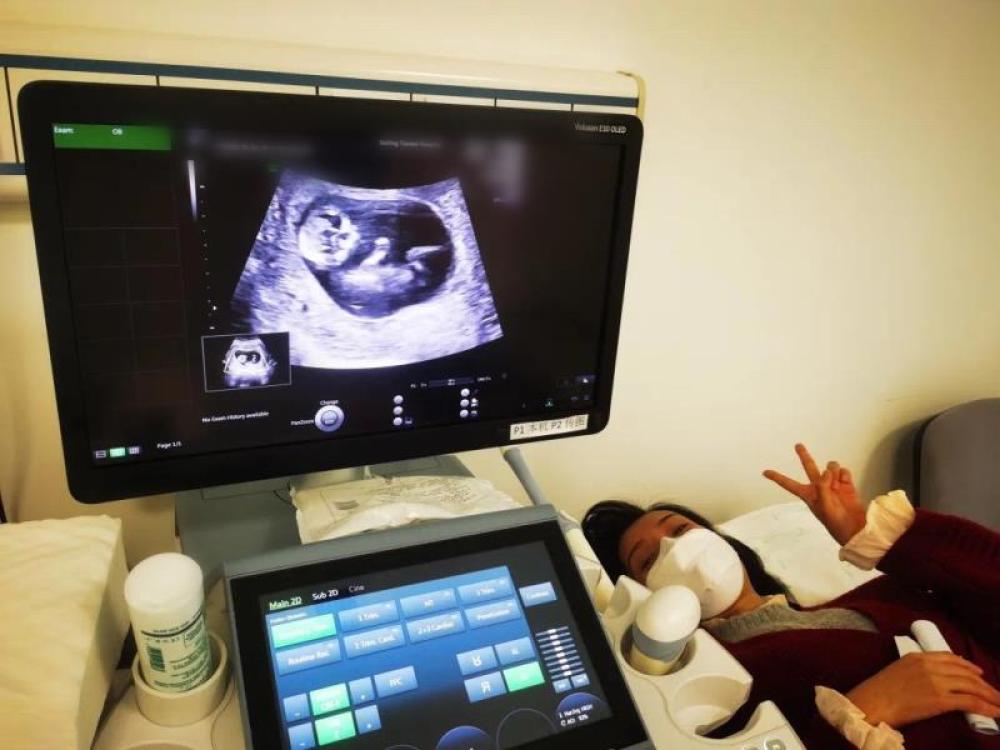

今天一早,妻子去醫(yī)院進(jìn)行B超檢查,同事用手機(jī)拍攝下了B超顯示屏上的畫面,記錄下了這個87天的小家伙第一次“亮相”。

圖為北京天壇醫(yī)院袁磊愛人做B超檢查。

“袁磊,看看你們家寶寶,可愛嗎?”收到同事發(fā)來的視頻,第一眼就看哭了,身邊的同事看完視頻也哭了。

視頻里,這個小家伙好像聽到了外面的召喚,在媽媽的肚子里伸手、踢腿、翻身,用各種動作進(jìn)行回應(yīng)……看到他那小胳膊小腿,一種從未有過的幸福感不停地向上涌,眼淚怎么也控制不住。

其實(shí)在武漢這么多天,他一直就是我的牽掛,今天終于看到他了,那種感受真是又緊張又激動,雖然還看不清他的樣子,但是已經(jīng)感受到他的活力。